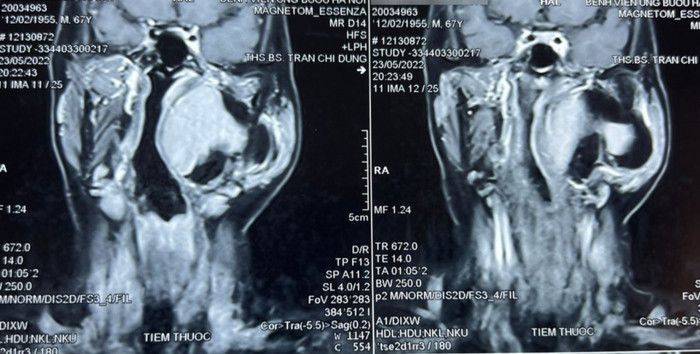

Hình ảnh chụp cộng hưởng từ khối u khoảng bên họng của bệnh nhân. (Ảnh: Bệnh viện Ung Bướu Hà Nội).

Khối u có đường kính lớn tới 10 cm nằm sâu trong khẩu kính thành họng, sát với nền sọ nên tiên lượng cuộc mổ rất khó khăn.

Khối u thuộc khoảng bên họng, trải dài từ nền sọ xuống hạ họng, đẩy lệch thành bên họng vào trong, gồm 2 phần: phần nông nằm dưới tuyến mang tai và phần còn lại nằm sâu hơn.Chẩn đoán sơ bộ ban đầu khối u là lành tính, ranh giới không rõ ràng.